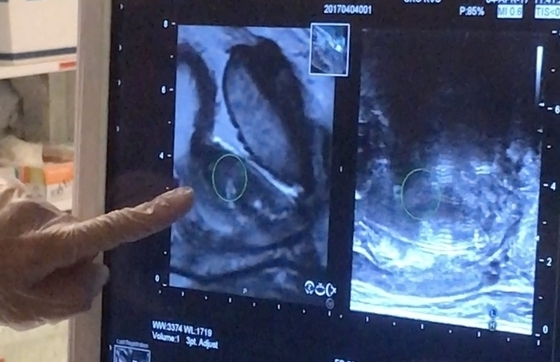

Un diagnóstico de cáncer puede afectar la vida de las personas de muchas maneras. La detección temprana del cáncer puede desempeñar un papel clave para ayudar a mejorar los resultados de salud y reducir los costos de atención médica.

Por ejemplo, la tasa de supervivencia de cinco años para el cáncer colorrectal cuando se detecta en sus etapas tempranas es superior al 90%. En las etapas más avanzadas, la tasa de supervivencia de cinco años para este tipo de cáncer es del 13% y el tratamiento puede resultar en efectos secundarios a largo plazo.

Comprender su riesgo puede ayudarlo a usted y a su médico a decidir cuándo comenzar ciertos exámenes preventivos y servicios de diagnóstico que pueden ayudarle a detectar cualquier problema lo antes posible, cuando el tratamiento pueda ser más eficaz.